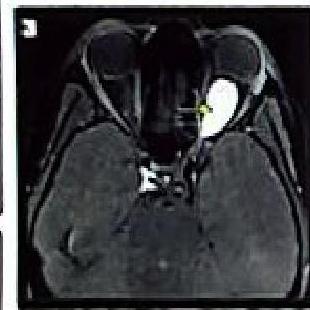

6. Optic Glioma

- The most frequently observed CNS tumor in NF1.

Diagnosis:

- MRI findings.

1. Bilateral Vestibular Schwannomas (Acoustic Neuromas)